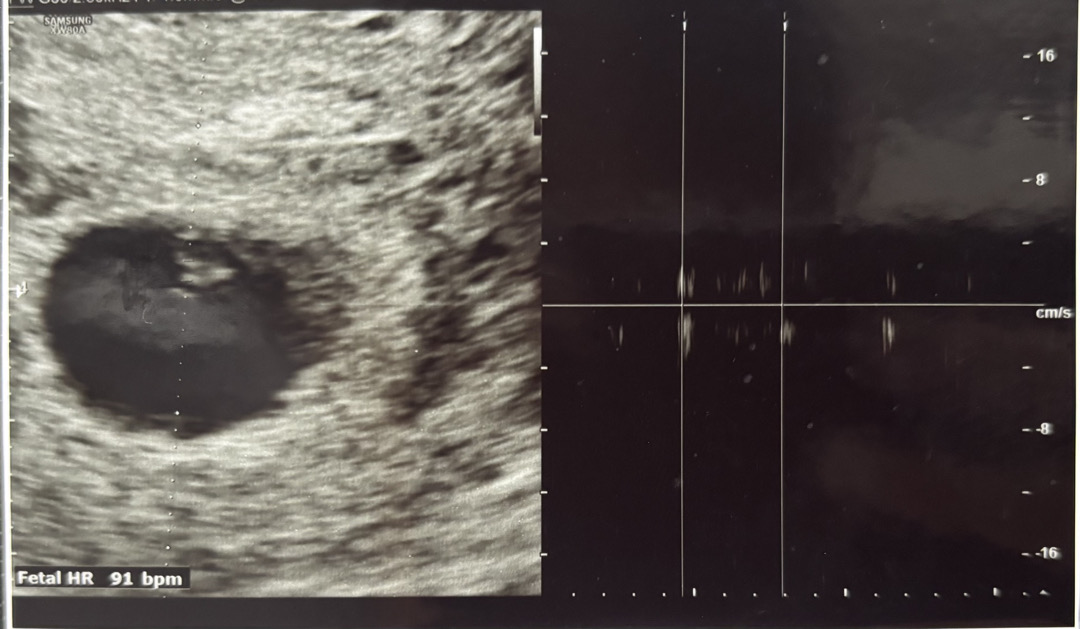

6주4일차

제가 현제 6주 4일차 심소 들으러 간 오늘 9월 30일 심장 소리 듣는데 심장이 느리게 뛰고 불규칙하다고 하시네요 그러더니 유산될 수도 있나고 하는데 너무 불안하고 무섭고 걱정이에요..ㅠㅠ